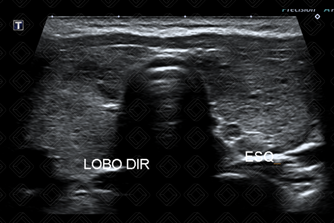

Texto alternativo para a imagem Figura 2. Créditos: Dra. Elazir Mota - Rio de Janeiro/RJ

Descrição das figuras 1 e 2: Ultrassonografia de tireoide evidenciando glândula aumentada, heterogênea, contendo algumas áreas hipoecoicas mal definidas. Ao color Doppler, observa-se aumento difuso da vascularização do parênquima glandular.

• Ultrassonografia de tireoide: Os principais achados são aumento glandular difuso, com parênquima tireoidiano apresentando textura heterogênea, contendo múltiplos pequenos nódulos hipoecoicos, refletindo a infiltração por tecido linfoide e degeneração folicular. Na maioria dos casos, há aumento da vascularização no estudo com Doppler colorido. Em fases mais tardias da doença, a glândula tireoidiana pode apresentar dimensões reduzidas e hiperecoica, com vascularização reduzida ao Doppler colorido, traduzindo evolução para atrofia e fibrose (figura 2).